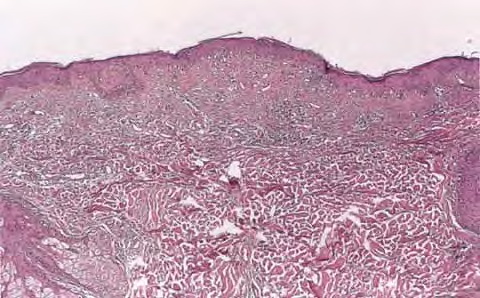

Histopathology. The erythematous-edematous lesions of the skin in dermatomyositis may show only nonspecific inflammation. However, quite frequently the histologic changes are indistinguishable from those seen in SLE. There is epidermal atrophy, basement membrane degeneration, vacuolar alteration of basilar keratinocytes, a sparse lymphocytic inflammatory infiltrate around blood vessels, and interstitial mucin deposition . With severe inflammatory changes, there may be associated subepidermal fibrin deposition. Although immune complexes are not detected at the dermal-epidermal junction as in lupus erythematosus, it should be

remembered that up to 50% of subacute cutaneous lupus biopsies can also have a negative direct immunofluorescence.

Old cutaneous lesions with the clinical appearance of poikiloderma atrophicans vasculare usually show a bandlike infiltrate under an atrophic epidermis with hydropic degeneration of the basal cell layer (see also the section on poikiloderma atrophicans vasculare). The Gottron’s papules overlying the knuckles also show vacuolization of the basal cell layer but acanthosis rather than epidermal atrophy . Subcutaneous tissue may show focal areas of panniculitis associated with mucoid degeneration of fat cells in early lesions. Extensive areas of calcification may be present in the subcutis at a later stage .